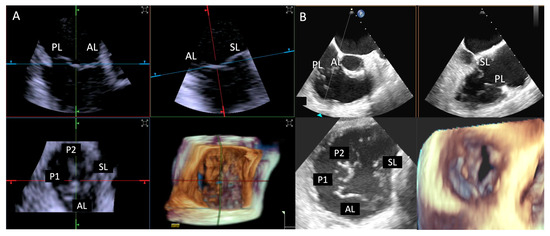

- Step number 3: steering and valve approach.

- Step number 4: ensuring perpendicularity and correct trajectory.